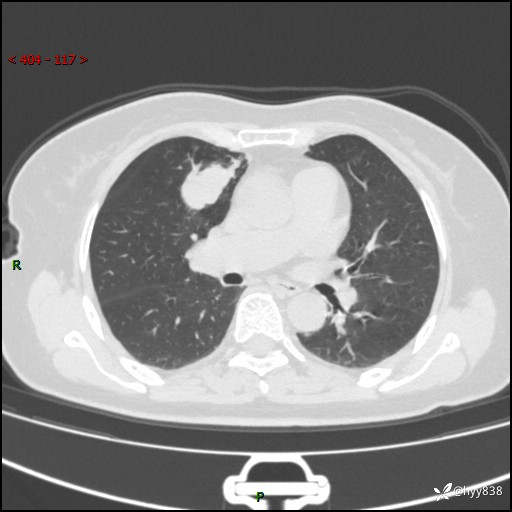

70岁/女,发现右上肺肿物10天。患者过敏体质,只有平扫,错过了一定可惜---结果公布~

【患者信息】:70岁/女

【主诉】:发现右上肺肿物10天

【现病史及既往史】:者10天前因“背部酸痛”于当地治疗,无发热,无呕吐,无头痛头晕等不适,胸部CT示右上肺肿物。遂来我科就诊,门诊看过病人后以“”收入我科, 自患病以来,精神、饮食、睡眠尚可,大小便正常,体力体重无明显减轻。

【检查】:胸部CT平扫(患者过敏体质,不能增强)